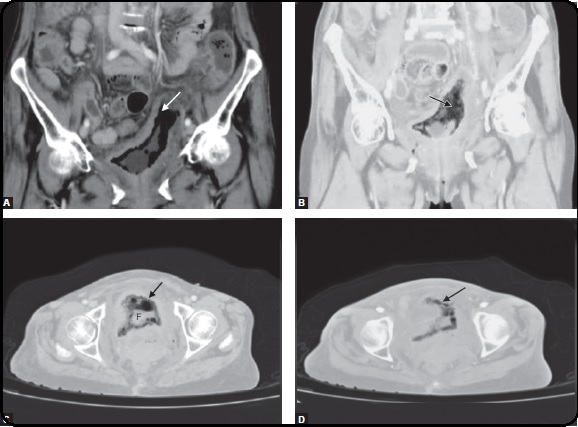

Gas in the Bladder: A Nightmare

Swati Kanchan, Richa Chouksey, Lakshmikant HK, Shripad Hebbar, Christian Fuenfgeld, Deeksha Pandey

P: 51 - 54